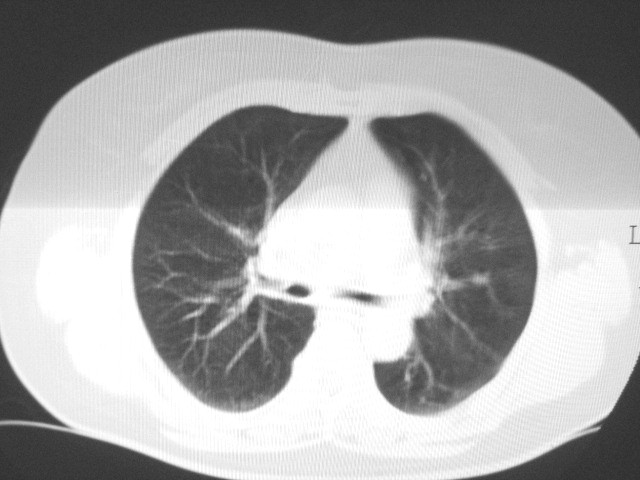

以下是引用清清楚楚在2007-8-28 7:13:00的发言:[br]右肺下叶可见斑片状高密度影,边缘模糊;右肺中叶内侧段及左肺舌段亦可见小斑片状模糊影。[br]考虑双肺感染,建议抗炎治疗后复查。

以下是引用天南地北在2007-8-27 23:49:00的发言:[br]右肺下叶可见斑片状高密度影,边缘模糊;右肺中叶内侧段及左肺舌段亦可见小斑片状模糊影。[br]考虑双肺感染,建议积极抗炎治疗后复查。

以下是引用天南地北在2007-8-27 23:49:00的发言:[br]右肺下叶可见斑片状高密度影,边缘模糊;右肺中叶内侧段及左肺舌段亦可见小斑片状模糊影。[br]考虑双肺感染,建议抗炎治疗后复查。

以下是引用难听在2007-8-28 13:17:00的发言:[br]右肺下叶背段支气管狭窄,是否可以考虑新生物伴阻塞性肺炎.请大家帮帮忙,这个病人是卫生局长的丈母娘.惹不起啊.